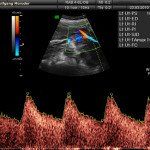

L’ecografia è una tecnica che consente di vedere gli organi del nostro corpo con l’utilizzo di onde sonore ad alta frequenza (ultrasuoni, non udibili dall’orecchio umano) che attraversano i tessuti. La sonda ecografica invia impulsi di onde sonore nel corpo. Quando le onde sonore arrivano al feto mandano degli echi: tali echi (o onde di ritorno) sono trasformati in immagini sul monitor dell’ecografo. Con l’ecografia è quindi possibile osservare in modo dettagliato il feto.